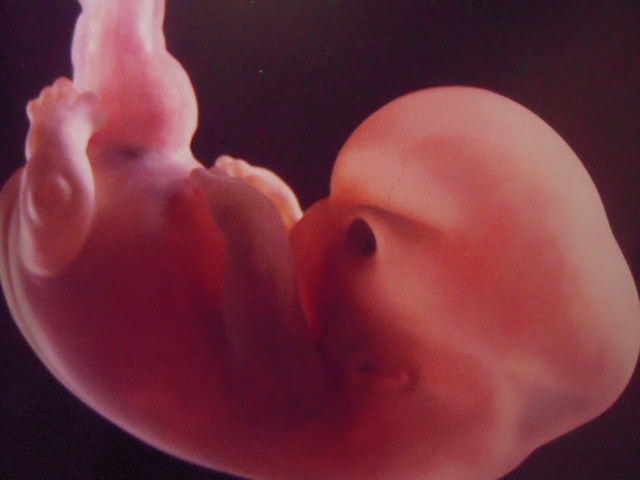

• semana 3, 4 y 5 de embarazo

semana 3, 4 y 5 de embarazo

En la semana tres se empieza a formar el sistema nerviso el embrión está formado por 3 capas célulares, la capa superior el ectodermo, donde se desarrolla el cerebro y varias regiones del sistema nervioso central, así como la epidermis las glándulas de la piel, uñas y el pelo. La capa media el mesodermo de donde cxrece el corazón, el sistema circulatorio, los huesos, los músculos, los riñones y los órganos de reproducción y por último la tercera capa mas interna , el endodermo, que es un tubo.